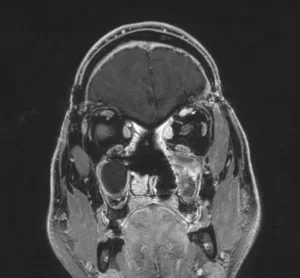

Ευμεγεθες Ακουστικό Νευρίνωμα με πίεση επί του εγκεφαλικού στελέχους

Ασθενής άνδρας, 48 ετών με συμπτώματα εμέτου και αδυναμίας από 15ημέρου περίπου. Στην αντικειμενική εξέταση διαπιστώθηκε σημαντική πάρεση προσωπικού νεύρου αριστερά και αστάθεια βάδισης &